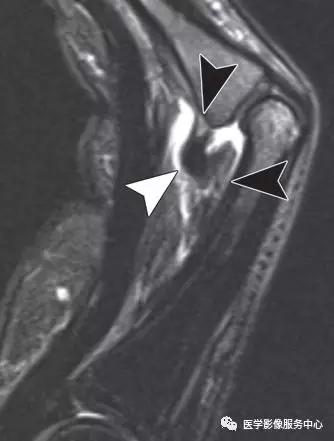

尺侧副韧带的撕脱损伤:

(左)第一指骨近端尺侧的尺侧副韧带撕脱骨折。

(中)白色箭头显示尺侧副韧带的全层紊乱,尺侧副韧带的正常解剖关系是位于内收肌腱膜(黑色箭头)的深部。

(右)Stener病变,伴尺侧副韧带损伤,撕脱的骨片被牵拉回缩(白色箭头)。